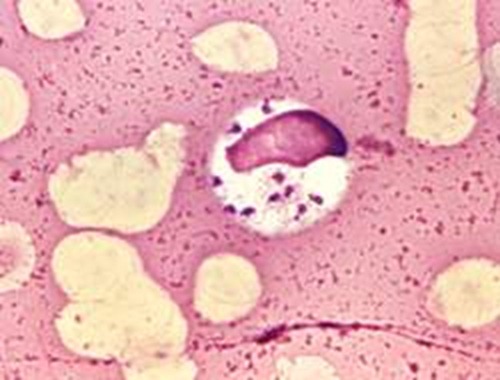

O parasita ataca principalmente os macrófagos, células que fazem parte do nosso sistema imunológico.

Sendo imune aos agentes químicos produzidos por nossas células de defesa, as leishmanias são englobadas pela célula, que acaba morrendo durante o processo de reprodução do parasita.

Ao prejudicar justamente as células responsáveis por atacar os corpos estranhos que invadem do organismo, o combate contra o parasita acaba sendo dificultado.

Levando em conta o ciclo biológico do parasita, os pesquisadores buscam desenvolver moléculas capazes de entrar no macrófago, para atingir o parasita no local onde ele se reproduz.